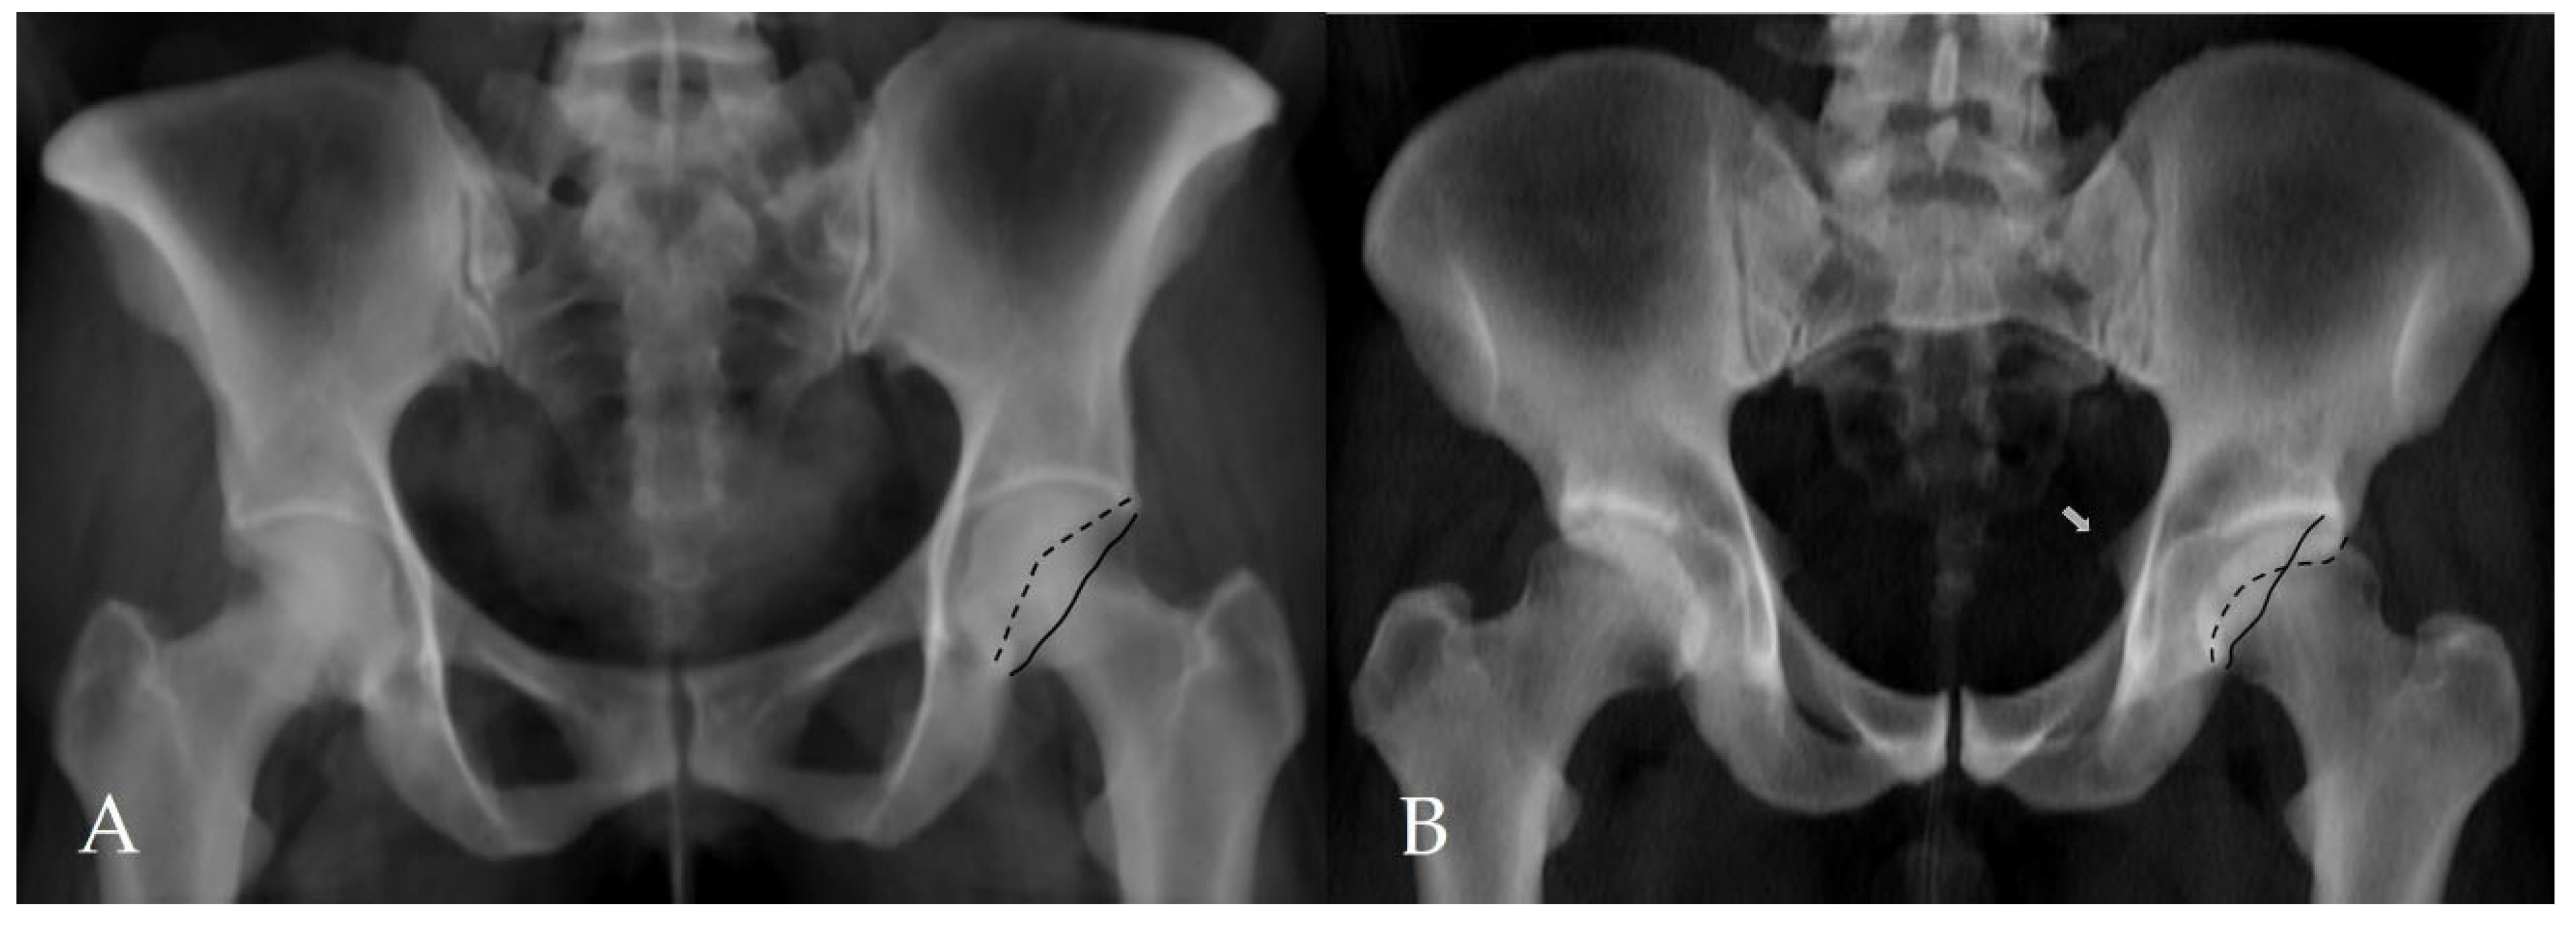

Figure 3. Assessment of additional morphological parameters of femoroacetabular impingement on a CT-based virtual pelvic radiograph. (A) Negative acetabular crossover sign. The black solid line represents the posterior acetabular wall, and the black dashed line represents the anterior acetabular wall. (B) Positive acetabular crossover sign with an associated ischial spine sign (white arrow), suggestive of pincer-type femoroacetabular impingement and acetabular retroversion.

The alpha angle and lateral center–edge angle (LCEA) were measured on CT. The alpha angle was assessed on axial oblique CT reformats parallel to the femoral neck axis as described by Nötzli et al., and the LCEA was measured using the CT-based coronal three-dimensional (3D) virtual pelvis radiograph model as used by Ergen et al. [13,14]. Acetabular coverage index (ACI) values were subsequently calculated using CT-MIP reconstructions. In all cases, angular measurements were complemented by a comprehensive morphological assessment for the presence of FAI, including evaluation of the crossover sign, posterior wall sign, ischial spine sign, and anterior wall lateralization (Figure 2 and Figure 3). CT was further used to evaluate the morphology of the acetabular rim, and acetabular overcoverage subtypes were determined [15]. The presence of underlying FAI and its specific subtype were determined by two radiologists in consensus. All measurements were independently repeated by both radiologists at a four-week interval. The senior radiologist had 20 years of musculoskeletal radiology experience, whereas the general radiologist had 5 years of clinical radiology experience. Prior to the measurements, the general radiologist underwent a one-week training period under the supervision of the senior radiologist. Statistical analyses were performed using the measurements obtained by the senior musculoskeletal radiologist. To assess intraobserver reliability, the senior radiologist recalculated ACI measurements after a minimum interval of two months. Prior to initiating angular measurements, the entire dataset was reviewed and verified by an independent radiology resident after deletion of all previous measurements and anonymization of cases. Subsequently, cases were randomly ordered to minimize assessment bias and ensure objective analysis. For primary statistical analyses, measurements obtained by the senior musculoskeletal radiologist were used to reflect routine clinical practice, while the second reader’s measurements were used exclusively for interobserver agreement analysis.